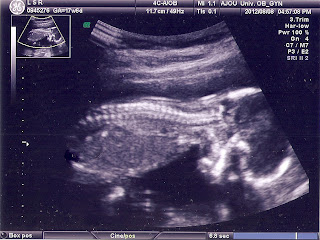

애기 초음파 사진 모음

초음파 사진이랑 입체 초음파 사진이랑은 차이가 크긴 하다.

하솔이 초음파 사진~~맘고생 했을때가 생각남...히히~~^^